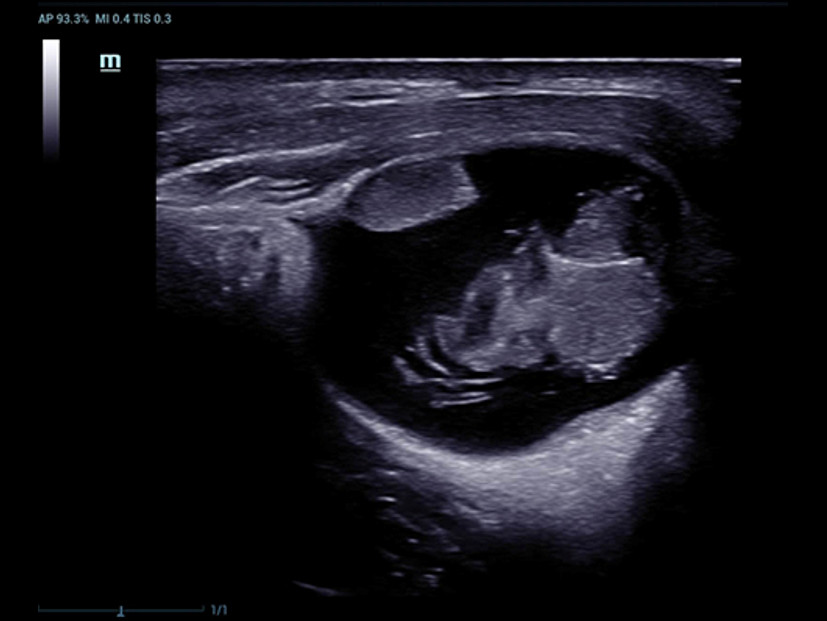

Fin dalla sua fondazione Mindray esplora continuamente nuovi modi per migliorare l'affidabilit├Ā diagnostica. Equipaggiata con la pi├╣ rivoluzionaria tecnologia ZONE Sonography?, la nuova piattaforma ZST+ di Resona 7 porta la qualit├Ā dell'immagine ecografica ad un livello superiore con l'acquisizione per zone e l'elaborazione dei dati canale.

Oltre alla qualit├Ā delle immagini di livello eccellente, Resona 7 migliora anche le capacit├Ā di ricerca clinica il rivoluzionario V Flow per la valutazione emodinamica vascolare, e l'acquisizione piani pi├╣ intelligente dal set di dati 3D per la diagnosi del sistema nervoso centrale fetale. Combinando il pi├╣ intuitivo funzionamento multi-touch basato su gesti e tutte le caratteristiche cliniche essenziali, Resona 7 sta veramente portando nuove tendenze nellŌĆÖinnovazione dellŌĆÖecografia.